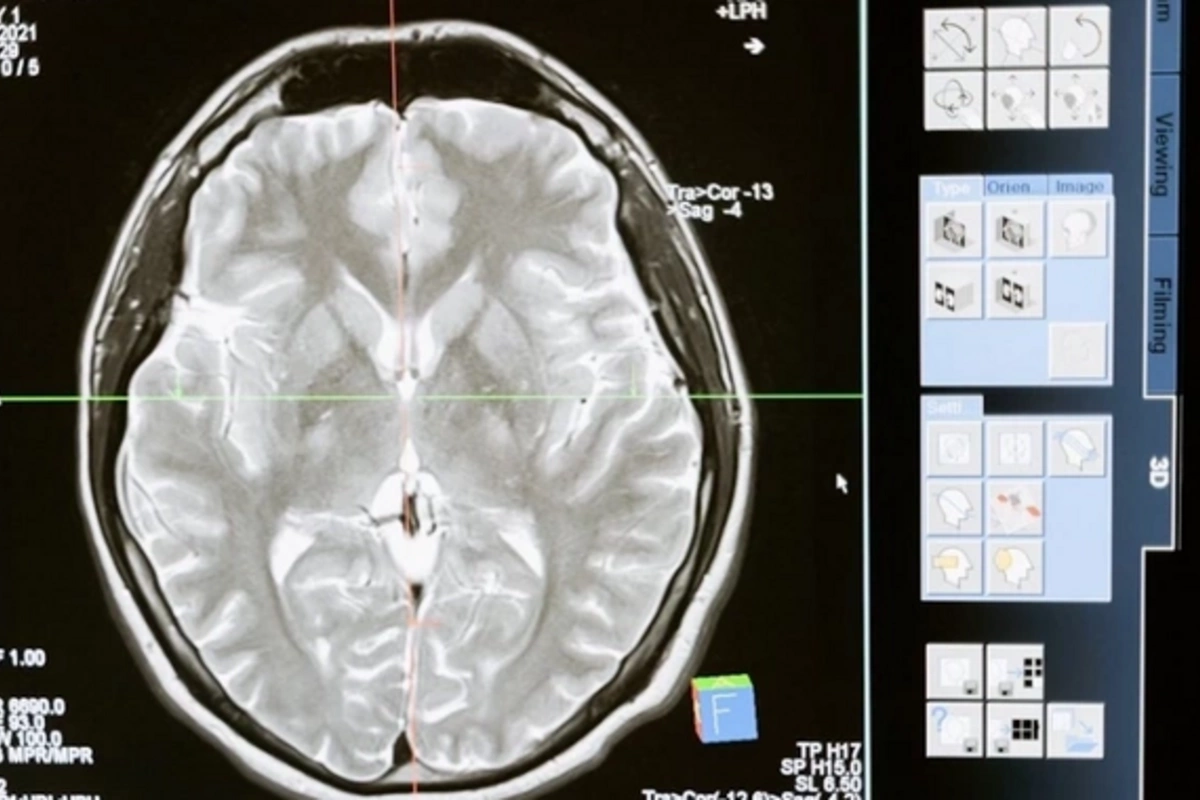

Глиобластома известна как особо агрессивная форма опухоли мозга, практически не поддающаяся традиционному лечению. Главная проблема - "иммунологическая холодность" опухоли, когда защитные силы организма не распознают угрозу. Учёные выяснили, что активация внутриклеточного пути STING может "разбудить" иммунитет, однако существующие препараты быстро разрушаются в организме и требуют хирургического введения непосредственно в опухоль.